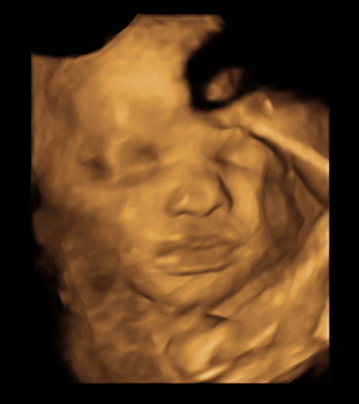

Just got back from my weekly ultrasound and 2 week doctor appointment. Everything still looks great for the both of us. She even flipped back head down from last week. We got some cute shots of her. Here are a few: (I love the one of her sticking her tongue out)

Had a 32 week ultrasound today to check the distance of my placenta to my cervix because it was too close at my 20 week scan. But, thank goodness, as my uterus stretched, my placenta moved up so I'm safe from a scheduled c-section! Woohoo! Also, everything else with baby looked good. He's head down, which means I've been rubbing and talking to his BUTT for the past couple weeks. Best part was the tech got us a couple 3D pics which we didn't expect. He definitely has daddy's flat bridge nose. him.